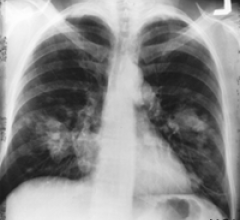

August 11, 2011 -- The New England Journal of Medicine's recent publication of the landmark National Lung Screening Trial (NLST), along with two congressional initiatives and an industry report, herald a much brighter future for lung cancer patients.